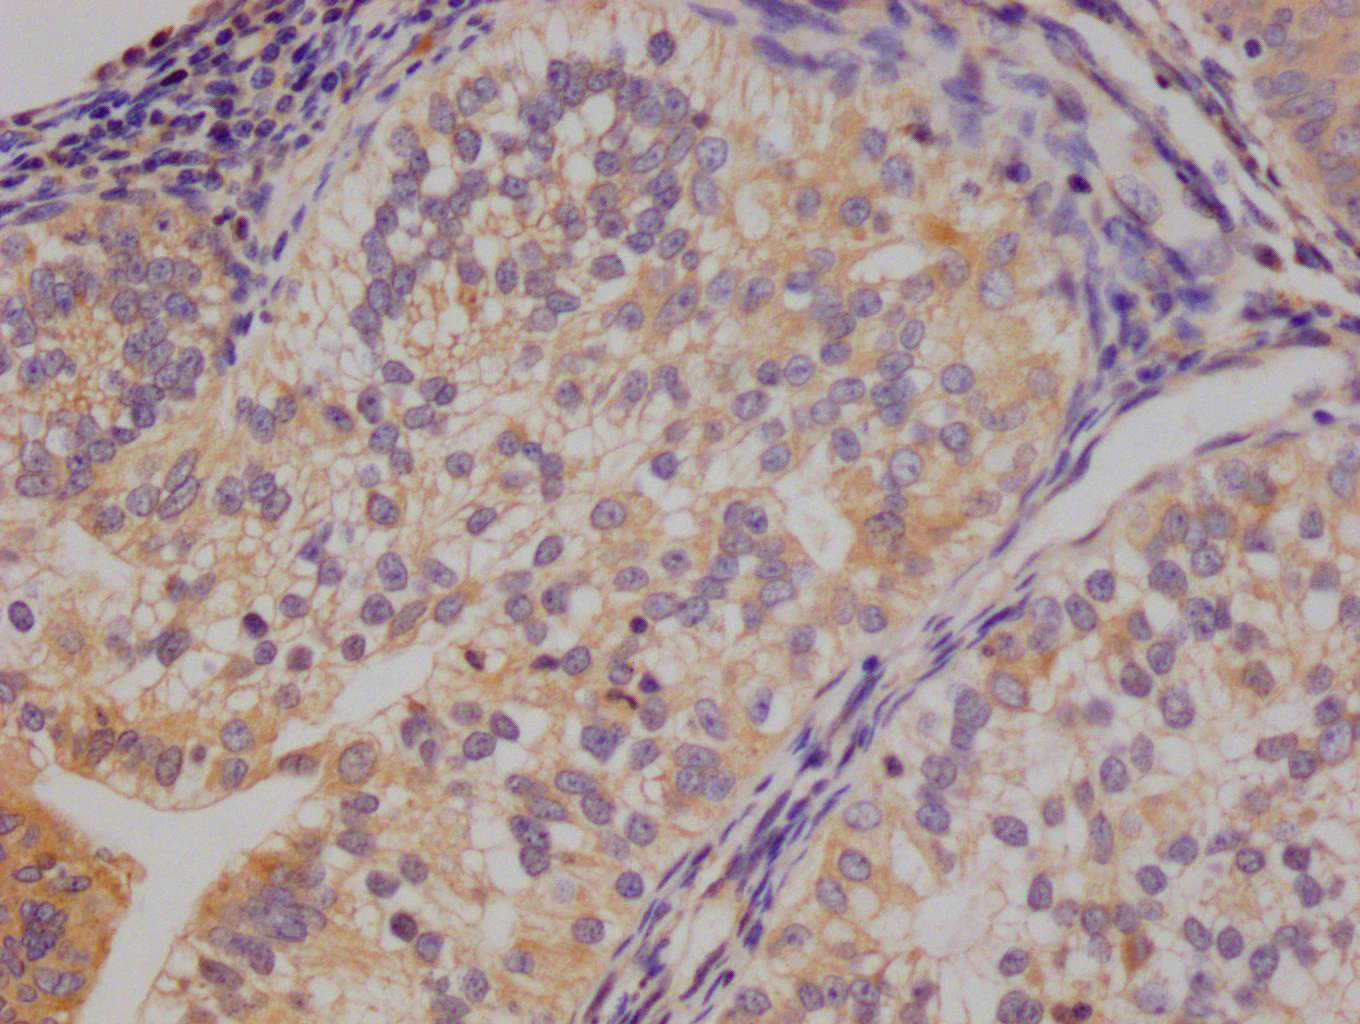

The image on the left is immunohistochemistry of paraffin-embedded Human gastic cancer tissue using CSB-PA196653(ABI1 Antibody) at dilution 1/40, on the right is treated with synthetic peptide. (Original magnification: ×200)